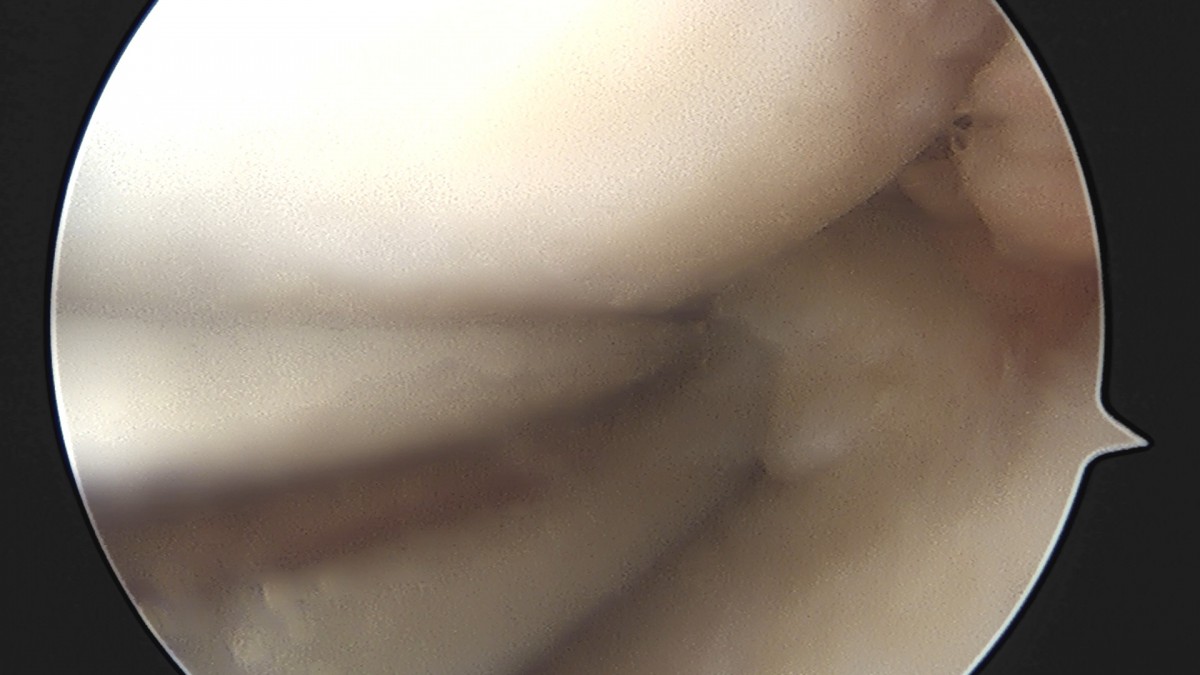

이재상원장님 무릎 반월상 연골판 절제술 박상O 환자

dae765e4d9ac96aee867c9d6292d8784_1758006444_2192.jpg